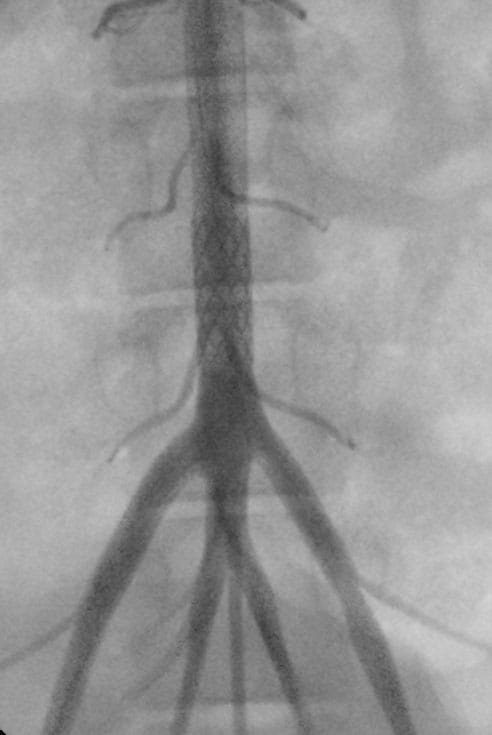

The plan for treating an infant with coarctation of the aorta would be to implant the ZeBRa stent in the coarctation segment of the aorta during the newborn period, Dr. Bocks says.

“The stent will provide complete relief of obstruction and will allow time for the aortic wall to model to an appropriate diameter matching that of the stent, after which the stent will degrade,” he says. “Many infants will likely need additional stenting with larger ZeBRa stents as complete remodeling might not occur for several years. However, this approach will obviate the need for higher-risk interventions, such as surgery or purposefully trying to fracture a rigid stent with an angioplasty balloon to ‘unzip’ it.”